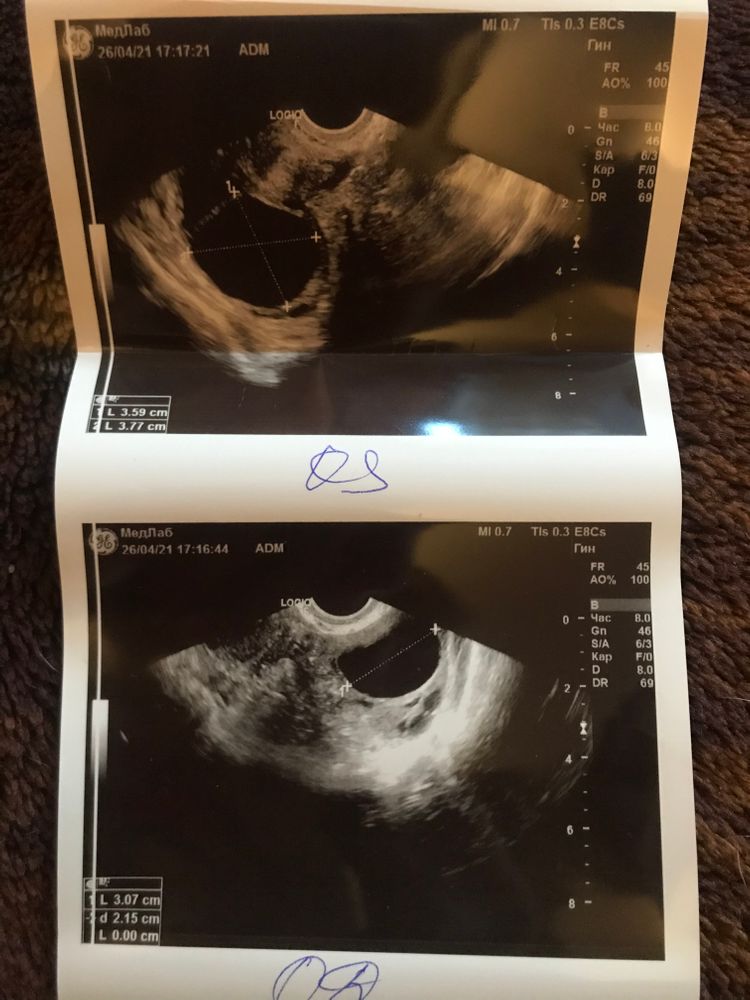

Так вот, немного отвлеклась, я хотела как можно скорее записаться на узи, ещё в субботу, позвонила, назначили на вечер понедельника(сегодня), ехала в такси и меня всю трясло, мне не давало покоя плохое предчувствие! Я зашла в кабинет, легла и когда она стала вводить во мне аппаратом - мне стало больно, я посмотрела на неё и увидела её удивление, как оказалось укол Овитрель(6500)мне не помог, как я и предполагала, и у меня в ЛЯ(он был один с ДФ) фолликул 35мм!!! Смотрим справа.. вырос тоже и уже составляет 28мм, шансов нет, слёзы, как же так??? Мне дали заключение, напечатали фото и сказали идти к врачу, завтра пойду..